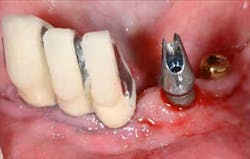

Figs. 1a and 1b: Initial situation of the 61-year-old female patient

Fig. 2: Remaining teeth in the upper right

Mandibular arch: the lower jaw is fully edentulous. Initially, according to the patient, an implant-supported five-unit bridge (23 to 27) was made on four implants (Alphabio®) placed in 2007. Tooth 22 was present at the time and a removable partial denture replaced the bilateral posterior missing teeth.

Then, in January 2012, tooth 22 was extracted and a second implant specialist placed a new implant (Zimmer Dental®) to replace it. The GP decided to use a Locator® attachment system on this new implant and have the existing denture stabilized over it, without paying any attention to the collapsing situation of the upper right.Fig. 3: CT scan shows the existing implants positions and the bone volume available